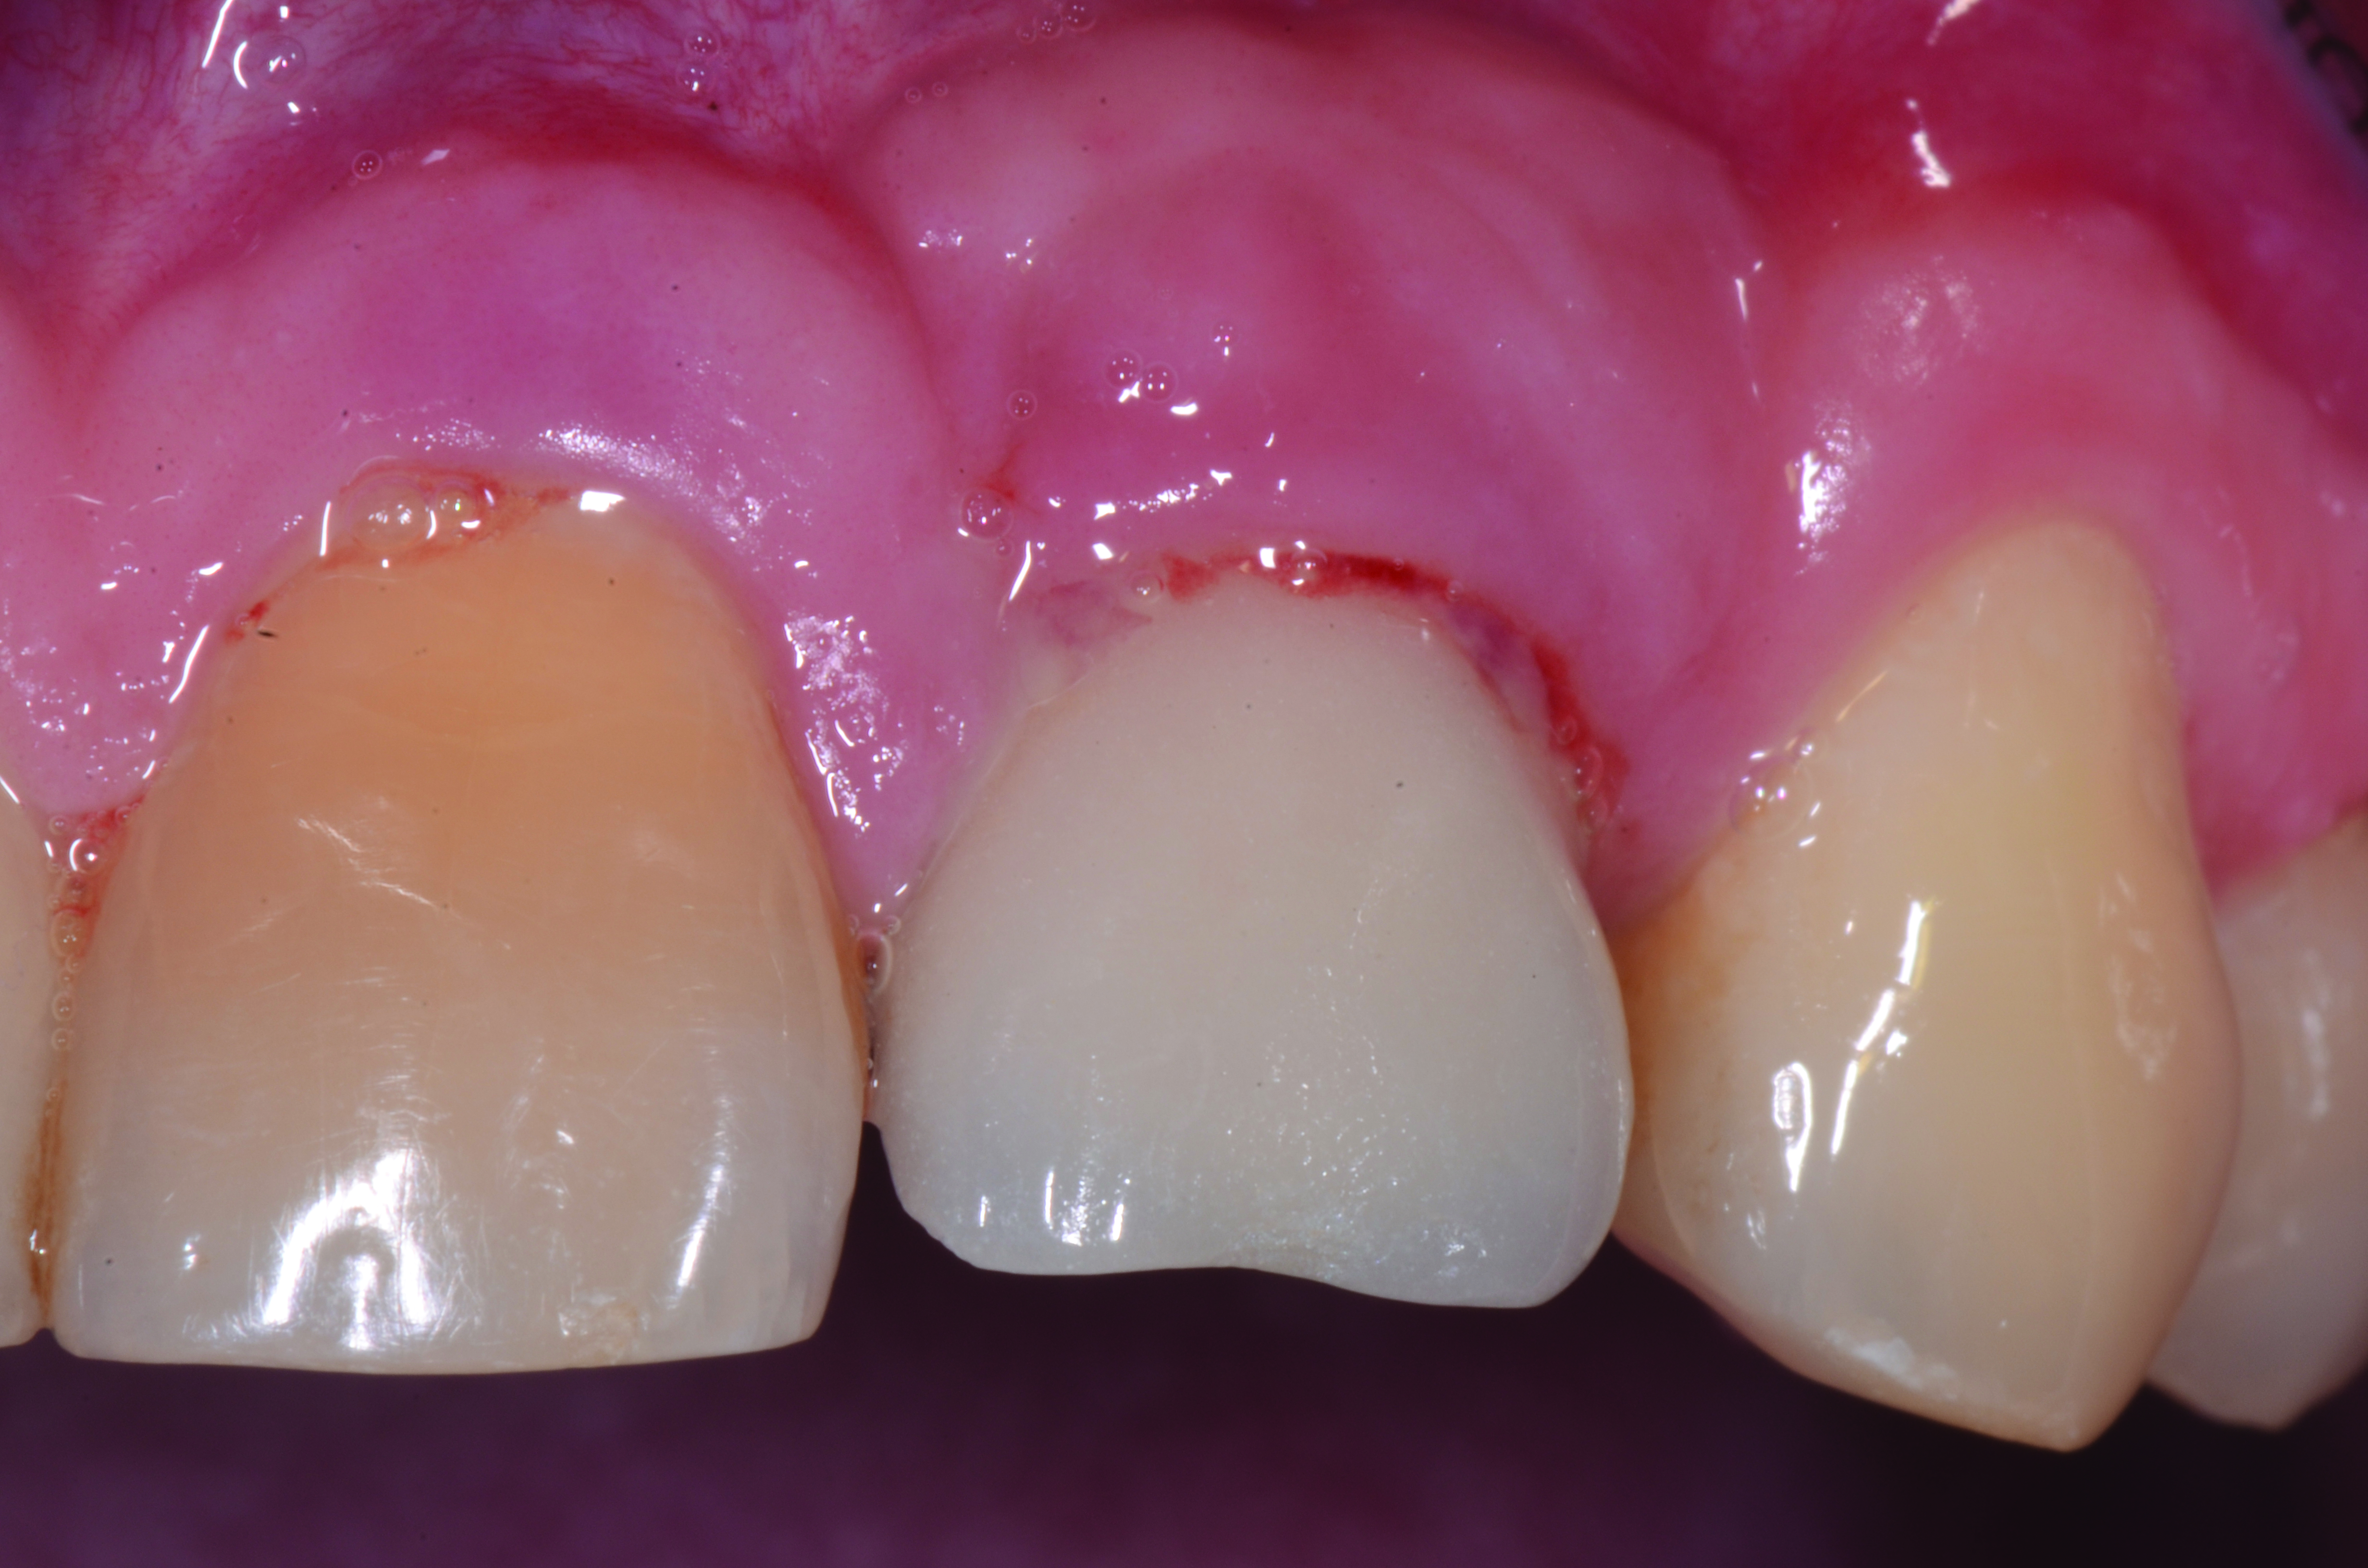

Clinical view of maxillary left lateral incisor implant in a healthy 48-year-old man. The swelling in the tissue surrounding this implant also bled on probing with depths up to 8 mm and exhibited purulence. The implant has been present for 14 years.

Figure 1

Radiograph of this same area. Note that there is no indication of bone loss and a long abutment collar. Hence, the diagnosis of peri-implant mucositis is given.

Figure 2